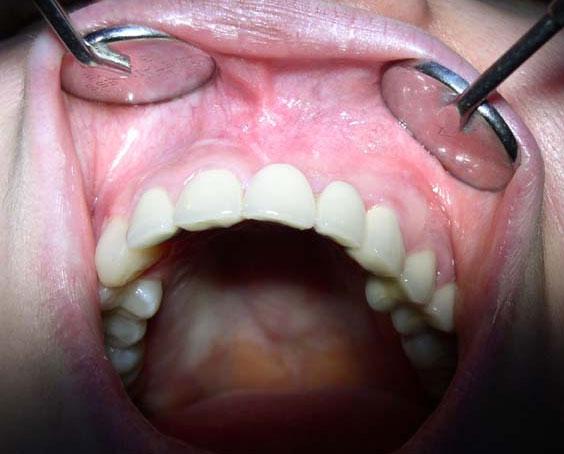

Короткая уздечка с легкостью обнаруживается при визуальном осмотре. Для этого просто нужно отвести верхнюю губу и рассмотреть место вплетения слизистого тяжа.

- Улыбка до и после пластики уздечки